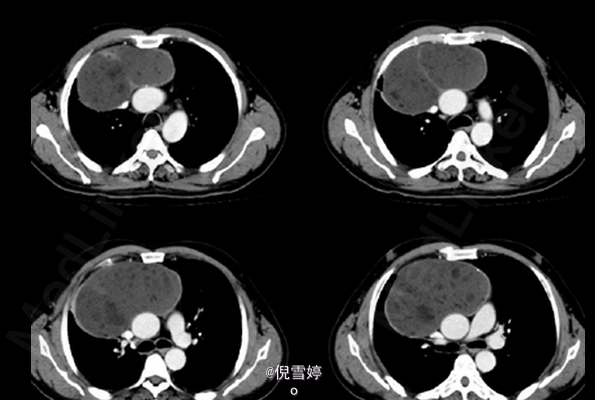

患者,男,49岁岁,因胸部不适2d就诊

患者除胸部不适外并无其他明显症状 辅查CT,右前纵隔囊性占位,多发脂肪样密度,病理检查良性

畸胎瘤 处理:手术切除